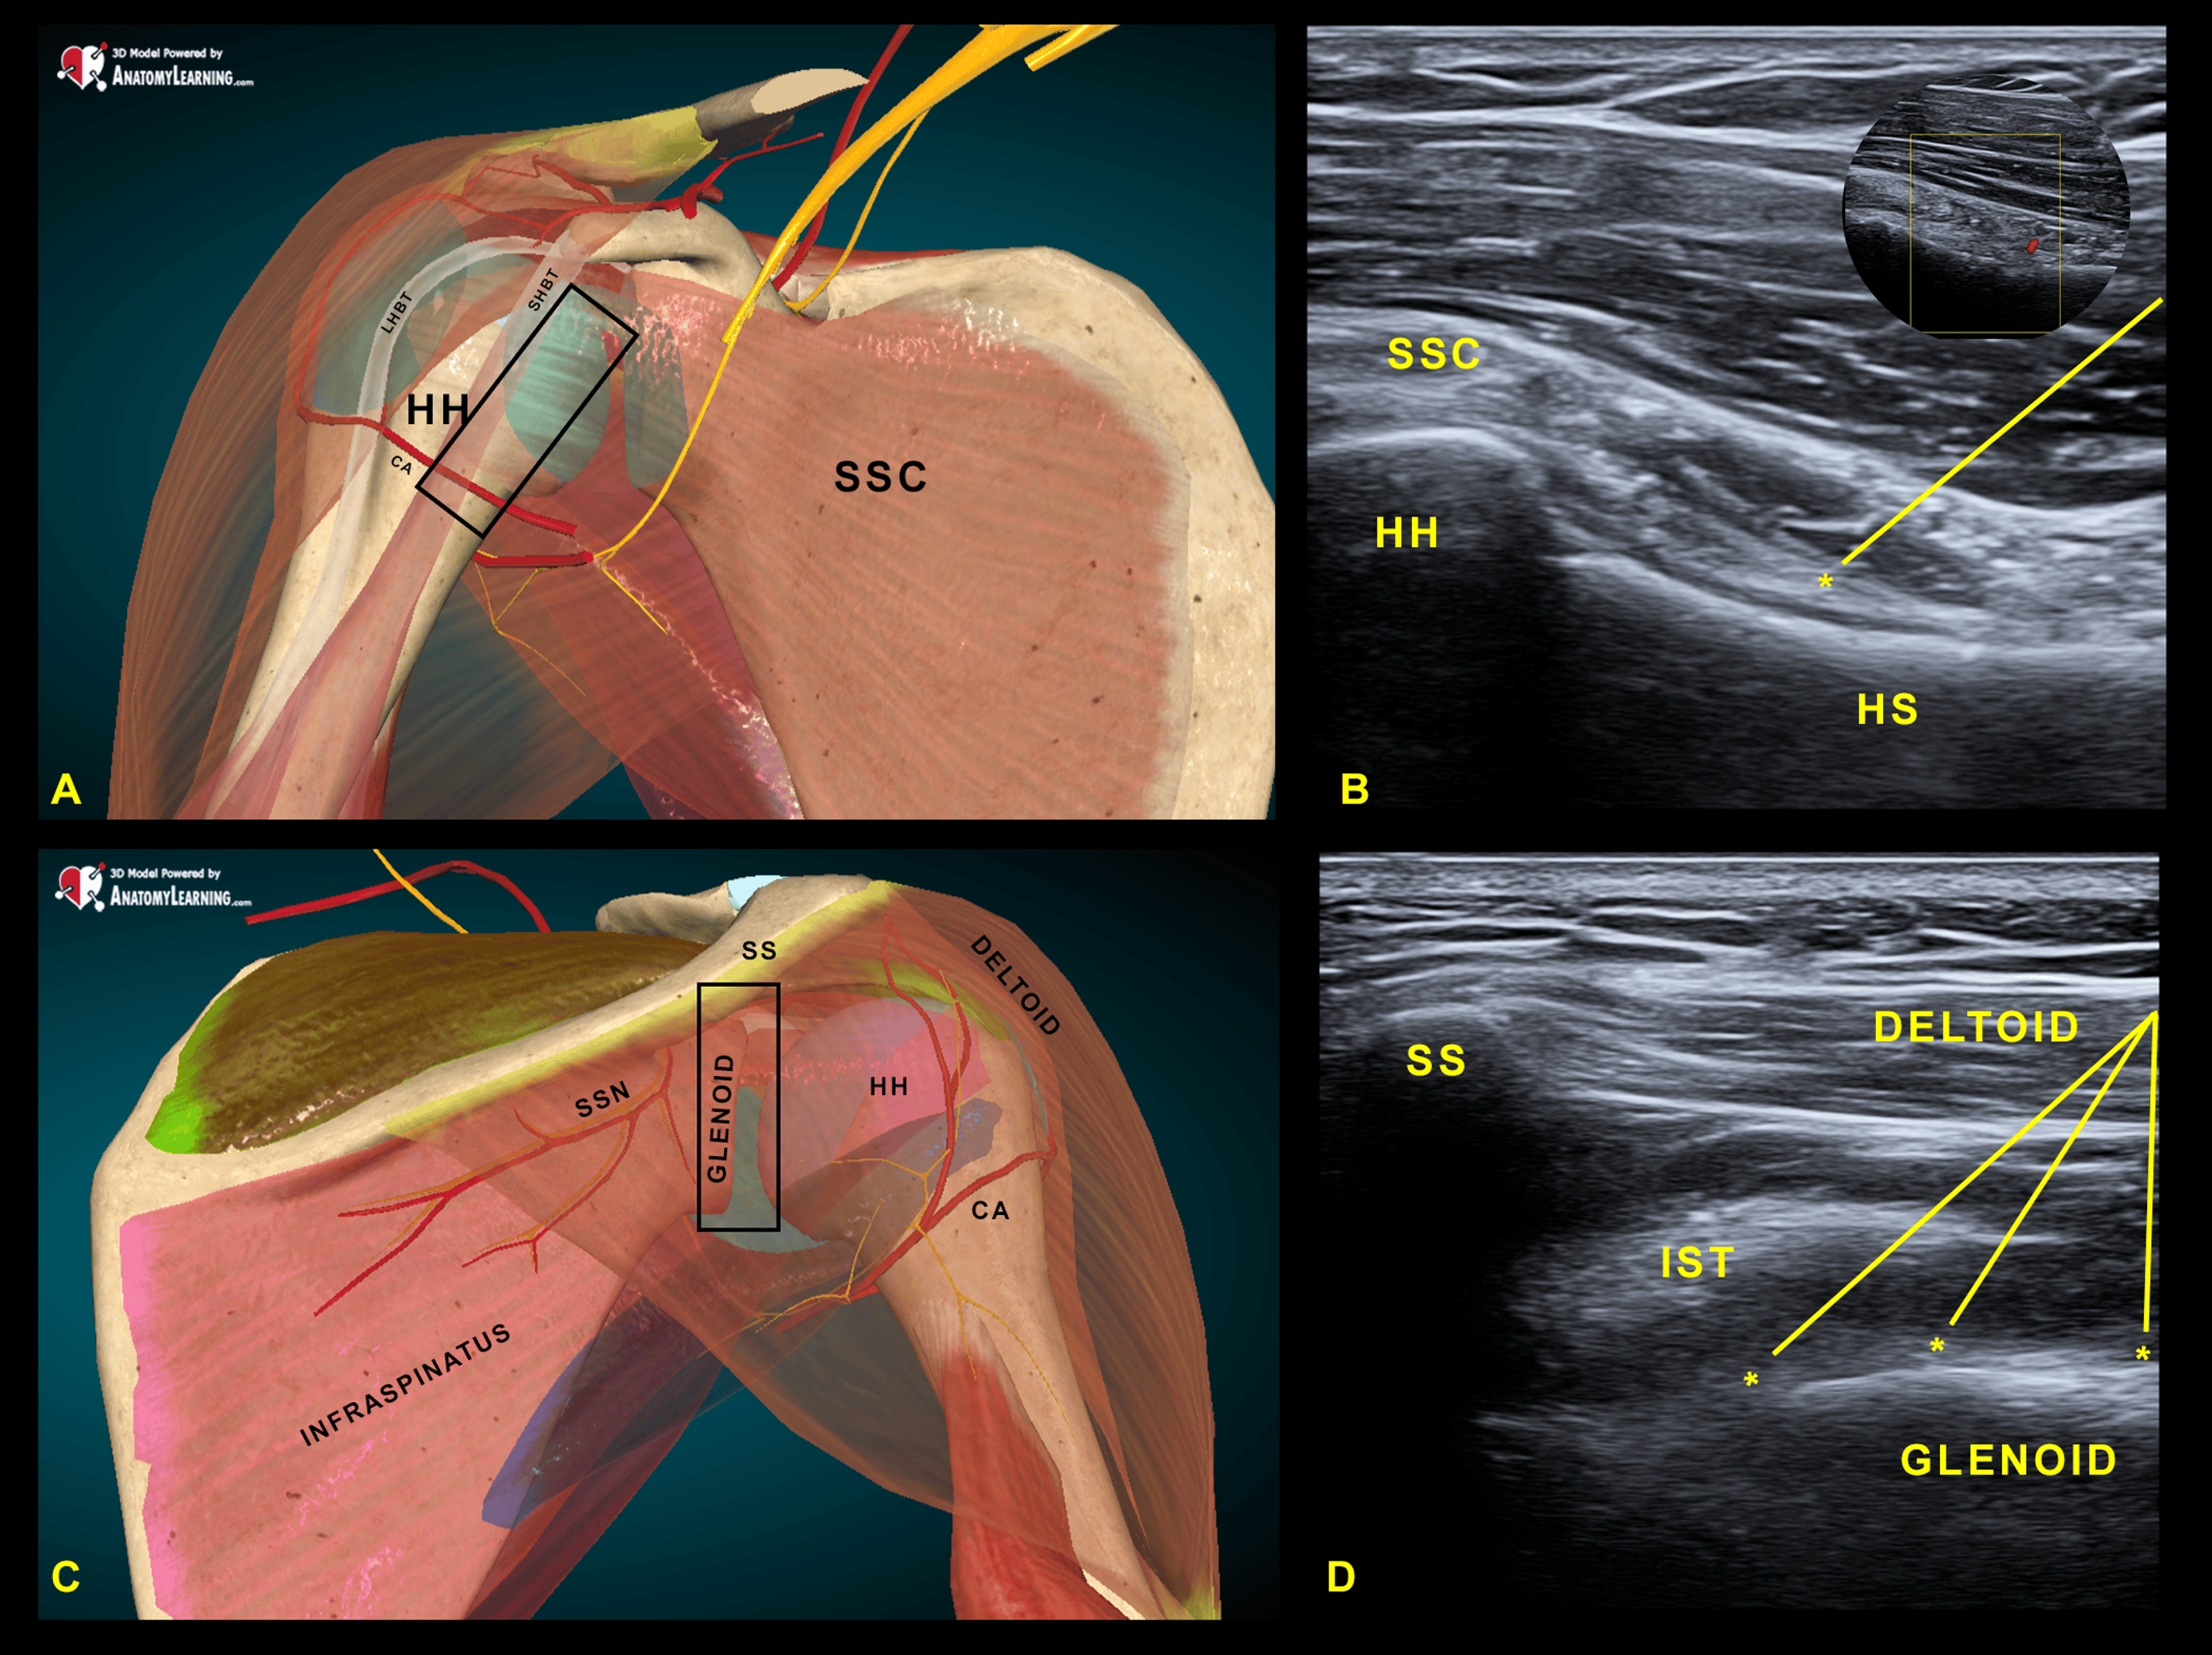

Role of ultrasound in clinical evaluation of shoulder Dr. Muhammad Bi…

From www.slideshare.net